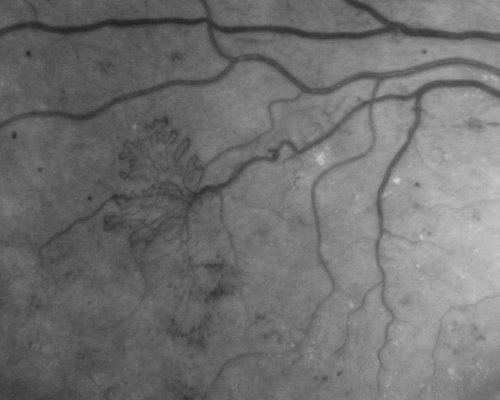

Proliferative Diabetic Retinopathy - Vitreous Hemorrhage and Tractional Retinal Detachment Left Eye

52-year-old man has been diabetic for nineteen years developed substantial vision loss over the last month or two. OD 20/70, OS 20/200.